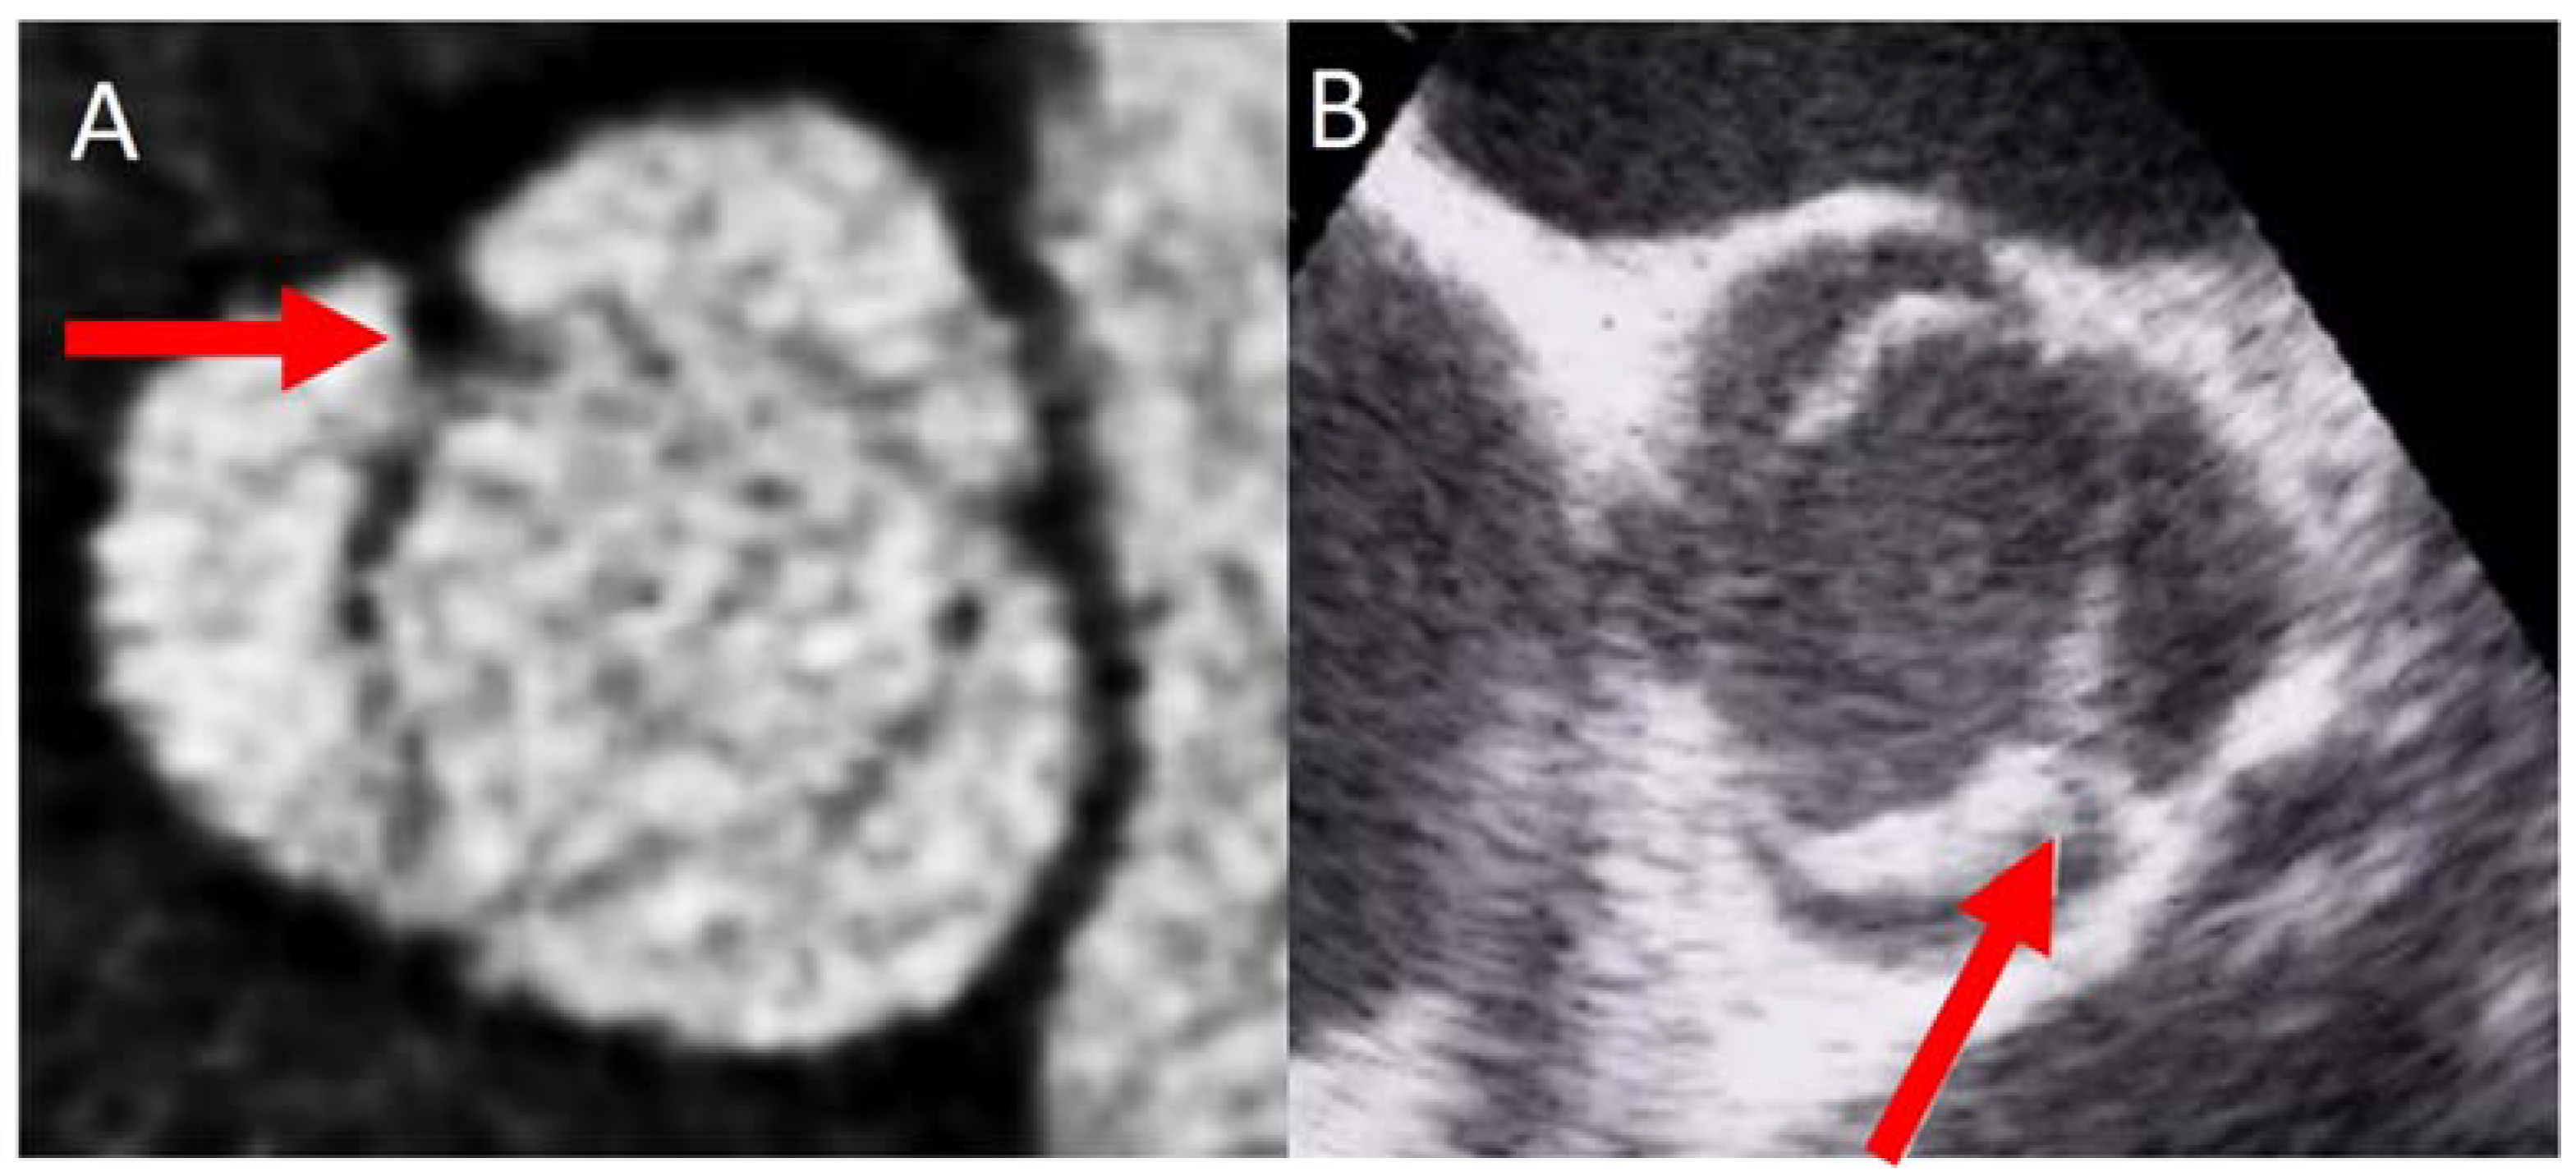

2. Diagnosis and BAV Phenotype

- Gleeson, T.G.; Mwangi, I.; Horgan, S.J.; Cradock, A.; Fitzpatrick, P.; Murray, J.G. Steady-state free-precession (SSFP) cine MRI in distinguishing normal and bicuspid aortic valves. J. Magn. Reson. Imaging 2008, 28, 873–878. [Google Scholar] [CrossRef] [PubMed]